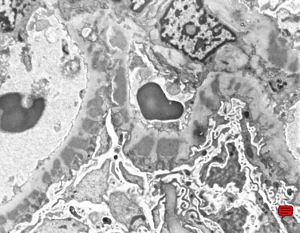

M,22y. | type II membranoproliferative glomerulonephritis